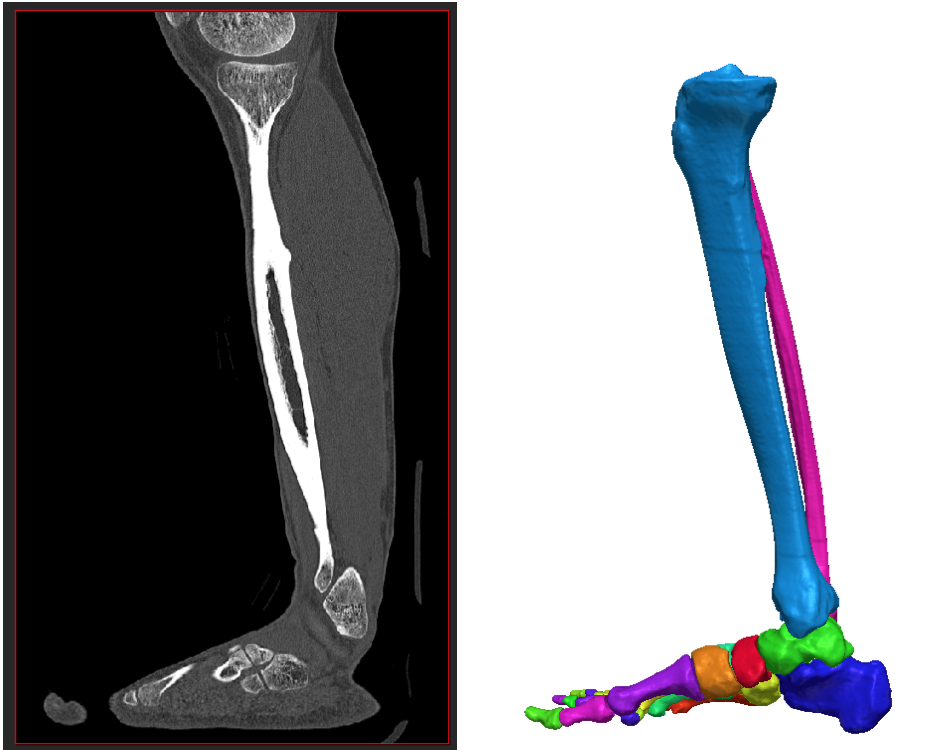

Au lieu de s’appuyer sur une approche géométrique, de masse ou générique, l’idée consiste à créer des modèles virtuels personnalisés à partir d’images du patient, puis d’utiliser une simulation réaliste afin de déterminer le traitement le mieux adapté.

- Plate-forme de simulation chirurgicale personnalisée, dotée d’outils d’analyse et de segmentation des images des patients, pour aider les chirurgiens orthopédistes à élaborer un plan chirurgical à partir d’une analyse précise des causes profondes de la maladie

Digital Orthopaedics permet à tous de vivre en bonne santé, promeut le bien-être de tous à tout âge, développe des infrastructures résilientes, soutient une industrialisation durable et favorise l’innovation. L’entreprise a pour ambition de transformer et d’optimiser la prise en charge des patients dans le domaine de la chirurgie orthopédique. 3DOXpert offre des services spécialisés intégrant les meilleures pratiques et la simulation, ce qui convient parfaitement aux médecins généralistes comme spécialisés. Le praticien peut générer un jumeau numérique du pied de son patient pour obtenir un rendu réaliste de la pathologie et mieux planifier l’approche chirurgicale.

Digital Orthopaedics est une start-up spécialisée dans les technologies de la santé. Son objectif ? Révolutionner la prise en charge orthopédique en planifiant et en personnalisant le traitement des patients grâce à la simulation. En créant des modèles virtuels 3D des pieds et des chevilles des patients à partir d’images médicales, l’entreprise permet aux chirurgiens de simuler les procédures, de prédire les résultats et d’adapter les interventions aux besoins anatomiques et fonctionnels de chaque individu.